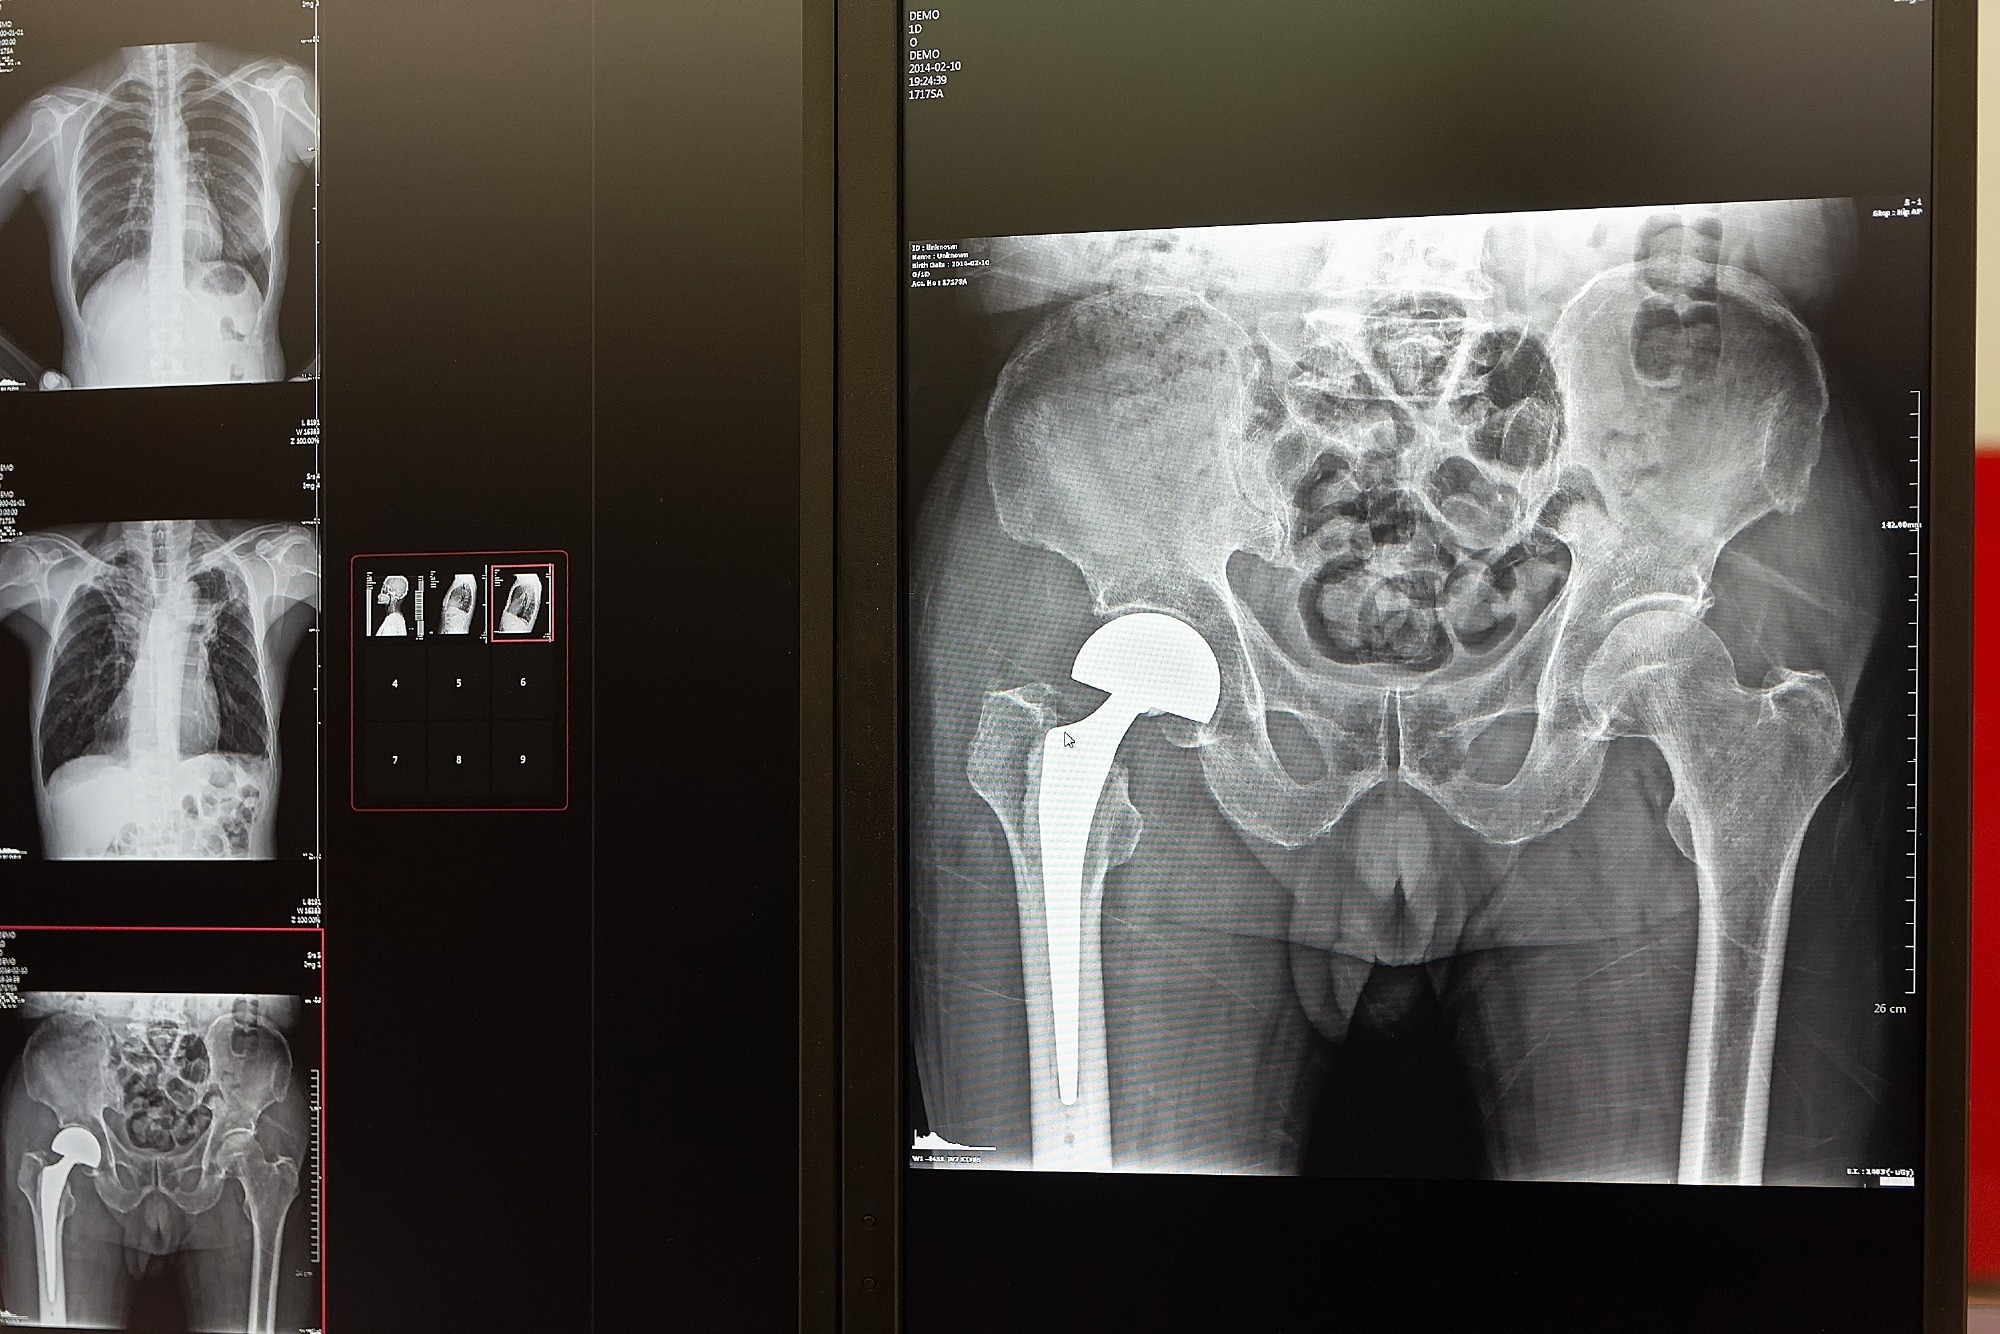

Тотальне ендопротезування кульшового суглоба, широко відоме як ендопротезування кульшового суглоба, — це хірургічна процедура, яка виконується для покращення рухливості у людей із серйозними травмами кульшового суглоба, багато з яких спричинені остеоартритом. Ця операція пов’язана з чудовими віддаленими результатами; однак післяопераційне відновлення та клінічні реакції різняться в окремих людей.

Поточне дослідження включало загалом 274 пацієнти з остеоартритом кульшового суглоба, які перенесли тотальне ендопротезування кульшового суглоба. Передопераційну інформацію щодо тривалості симптомів, інтенсивності болю, діапазону рухів стегон, сили м’язів нижніх кінцівок і швидкості вільної ходи на 10 метрів збирали за допомогою відповідних методів.

Повідомлені пацієнтами післяопераційні клінічні результати оцінювали за допомогою Оксфордської шкали кульшового суглоба (OHS) і оцінки забутого суглоба-12 (FJS-12). OHS – це опитувальник, який повідомляють пацієнти, для оцінки болю та функції кульшового суглоба, тоді як FJS-12 – це інструмент оцінки результатів, який використовується пацієнтом для оцінки обізнаності про штучний протез під час повсякденної діяльності після тотального ендопротезування кульшового суглоба.